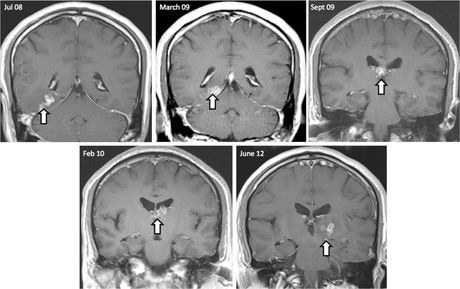

Jednom kada larve uđu u krvotok, mogu migrirati u različite organe. Ovo stanje, poznato kao cisticerkoza, može zahvatiti mozak, oči, mišiće i druga tkiva. Posledice uključuju jake glavobolje, epileptične napade, neurološka oštećenja, probleme sa vidom, pa čak i smrt. Procene govore da godišnje oko 50.000 ljudi širom sveta umre od komplikacija povezanih sa infekcijama pantljičarom, iako većina tih slučajeva nije rezultat namernog unosa parazita.